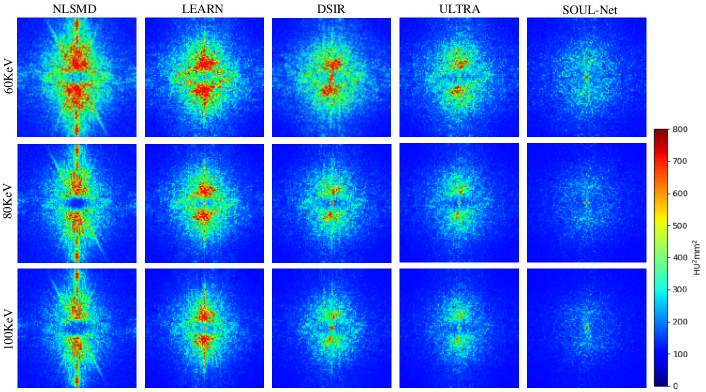

The NPS of all results are shown in Fig. 4. We can see that in both high- and low-frequency bands, the error in the results of SOUL-Net is lower than that of the other methods. This can be treated as additional evidence of the effectiveness of our proposed method.